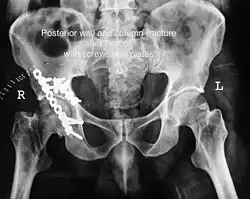

Posterior column As with posterior wall injury, this also typically occurs due to dash board injury. Posterior column + Posterior wall These fractures are extensions of elementary fractures. With the involvement of the posterior wall, the difficulty in treatment increases. These fractures are rarely amenable to non-surgical treatment. Due to posterior wall fracture, the hip is usually dislocated posteriorly, requiring immediate reduction of dislocation and surgical reconstruction after a few days.

The posterior column with posterior wall fracture occurs due to dashboard injury. The anteroposterior view may give clues to these injuries. Judet views and CT scans help in knowing the extent of the injury.

The final management depends on the size of the fragment(s), stability and congruence of the joint. In some cases traction for six to eight weeks may be the only treatment required; however, surgical fixation using screw(s) and plate(s) may be required if the injury is more complex. The latter treatment will be called for if bone fragments do not fall into place, or if they are found in the joint, or if the joint itself is unstable.

Innominate bone is a flat bone with many curves. In most part the bone is thick enough and has broad surfaces that are amenable to primary fixation using lag screw(s) and to neutralize forces across the bone one needs to add plate(s) on the surface of the fractured fragments for it to heal without deformity.

Implants : normally lag screws and reconstruction plates are preferred implants